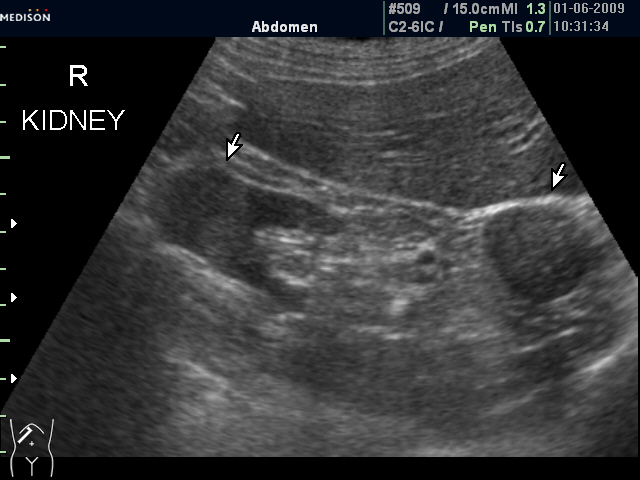

Женщина 72 лет. При УЗИ выявлены два аваскулярные образования: в нижнем полюсе правой почки и у верхнего полюса почки.

Уникальность случая в том, что эти изменения - БЕЗ ДИНАМИКИ с 2005 года.

Опухоль почки?

Опухоль почки и надпочечника.

Без допплера явно опухоль почки